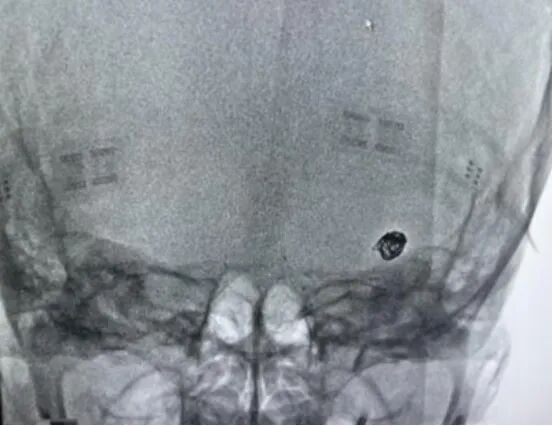

行左侧大脑中动脉M1段栓塞取栓术后,发现左侧大脑中动脉远端复通但重度狭窄近闭塞,分叉部见一动脉瘤,瘤nei射血明显,远端血管见显影。考虑狭窄部位随时可能再闭塞,而开通闭塞部位后动脉瘤破裂出血风险较大,故在术中行动脉瘤栓塞并狭窄部位支架置入血管成形。术中栓塞动脉瘤后左边脑氧突然下降至48%,再造影后,发现远端血管未见显影。

(惭翱颁-200脑组织氧饱和度监测仪提示:左脑氧饱和度下降至48%)

(造影提示:远端血管未见显影)